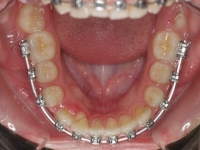

Clase II paciente 15 años

La paciente O.O. acude a nuestra consulta por:

– Canino 13 e incisivo lateral 42 en posición ectópica.

– Canino 23 incluido.

Con lo que decide realizarse un tratamiento de ortodoncia de duración de 24 meses con brackets damon Q.

CASO COMPLETO: